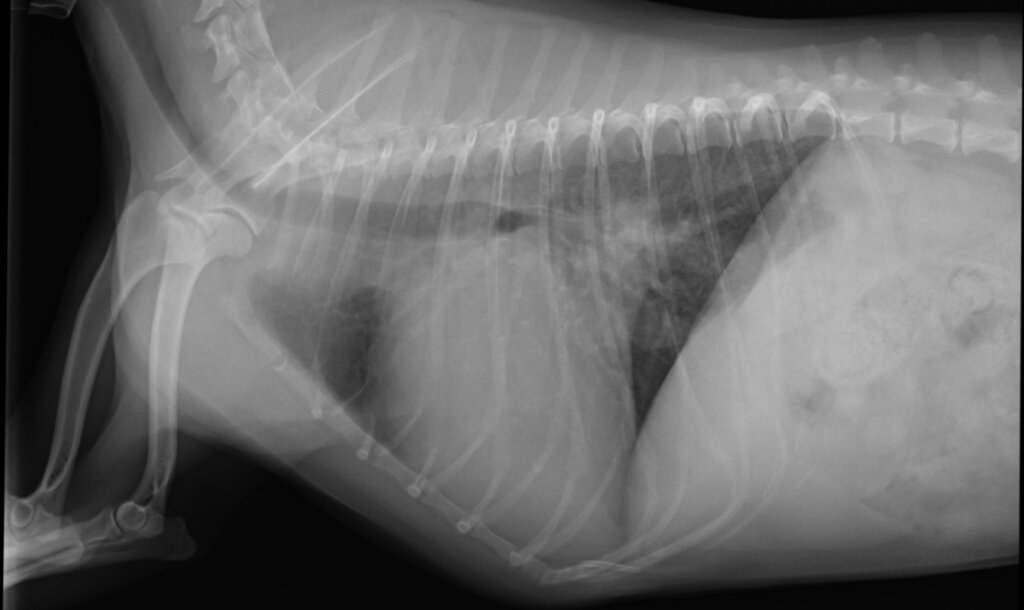

本症例は、重度の呼吸困難を主訴に来院しました。検査の結果、心原性肺水腫と診断されました。

■ 来院時の状態

来院後すぐに利尿薬および強心薬による治療を開始しましたが、呼吸状態は急速に悪化し、挿管管理が必要となりました。

高用量の利尿薬を必要とし、内科治療のみでは肺水腫を繰り返す状態であり、ACVIMステージDの粘液腫様変性性僧帽弁疾患(MMVD)と判断しました。

手術前